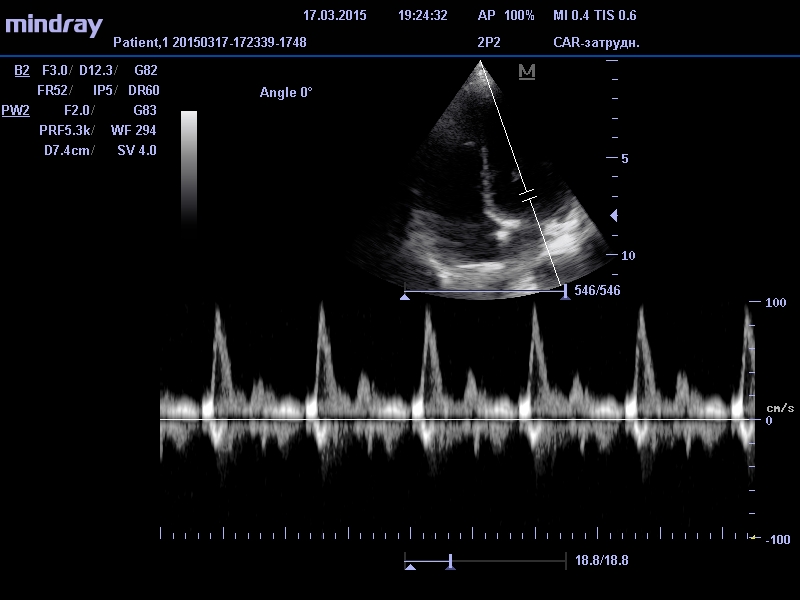

Смысл данной диагностической процедуры сводится к тому, что датчик посылает ультразвуковой сигнал (звуковая волна, которая не слышна человеческим ухом из-за своей невероятно высокой частоты) в область сердца. Из-за различной плотности тканей и расстояния ультразвуковые волны с различной скоростью отражаются от стенок сердца. Принимая обратный сигнал диагностический аппарат выстраивает картинку исследуемого органа.

Основными показателями, на которые обращают внимание специалисты-кардиологи при постановке диагноза больному, являются параметры правого и левого желудочка сердца, а также толщине перегородки между ними. Наиболее важные характеристики, это - масса сердечной мышцы, объем в состоянии покоя и объем в момент сокращения миокарда, количество выбрасываемой в результате сокращения крови. Эти данные специалист сравнивает с нормативами здорового человека, из чего делает выводы о состоянии здоровья кардиосистемы наблюдаемого пациента.